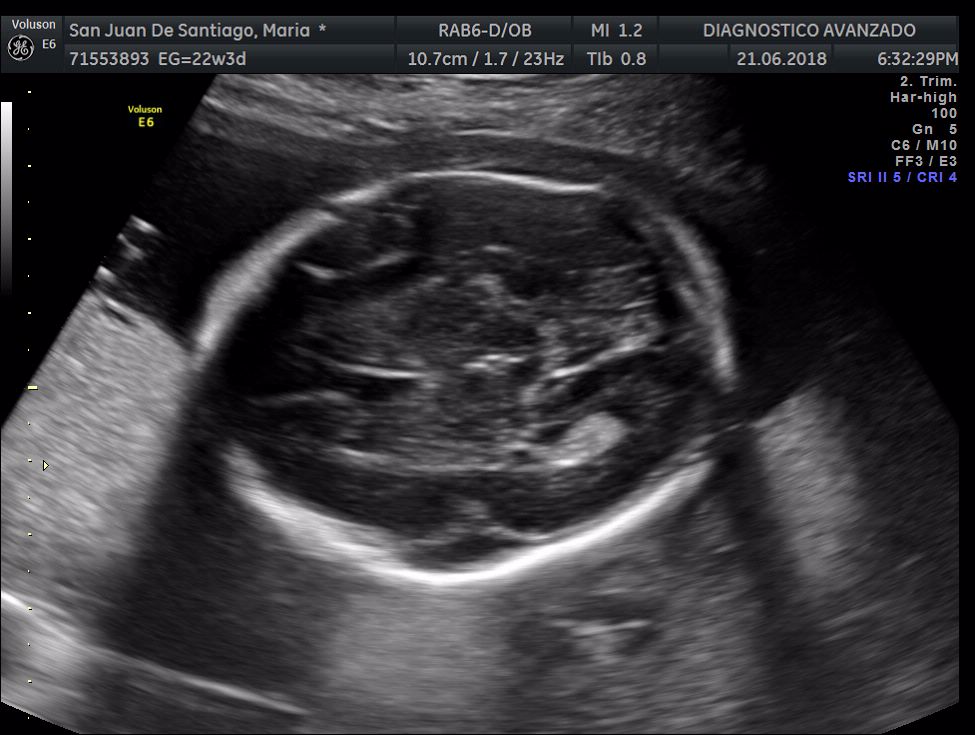

¡Hola a todos! Hoy hemos ido a hacer la tradicional ecografía 3D de la niña, os dejamos todo el material (aunque es un poco demasiado).